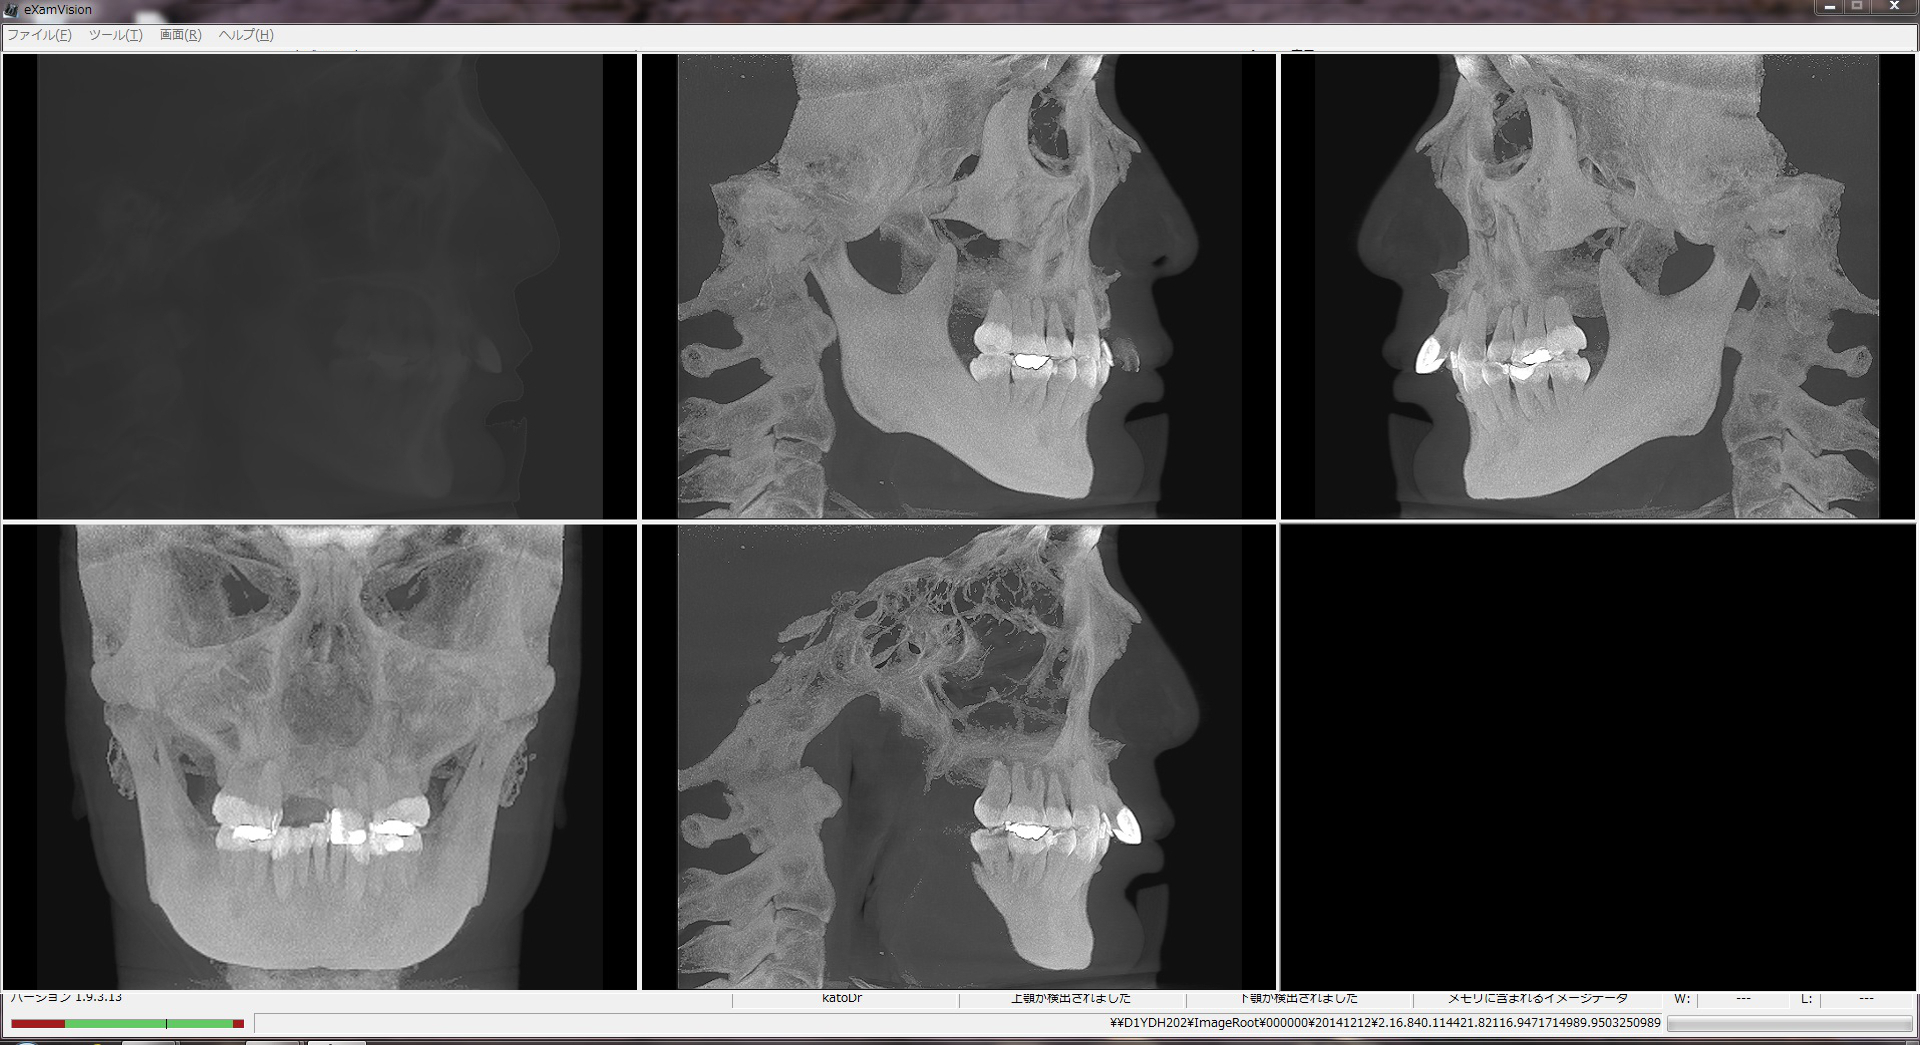

CT撮影

加藤歯科医院では最新のCT撮影機器・3D画像データ解析システムを導入し、小矯正治療時に活用しています。

A)CT画像

撮影したCTデータを編集し、セファロを表示したり、特定部位を拡大・着色したりすることができ、これらの情報をもとに診断を行います。

B)3D画像データ解析

撮影した3D画像データに矯正治療に特化した加工をします。矯正に必要な基準点をポイントすることで、顔のラインや2点間の距離および2線の角度などを計測し、精密な情報を取得します。また、顔貌を貼り付けた3D像や抜歯・矯正による歯牙の除去・移動のシミュレーション、矯正後の顔貌予測なども行えます。